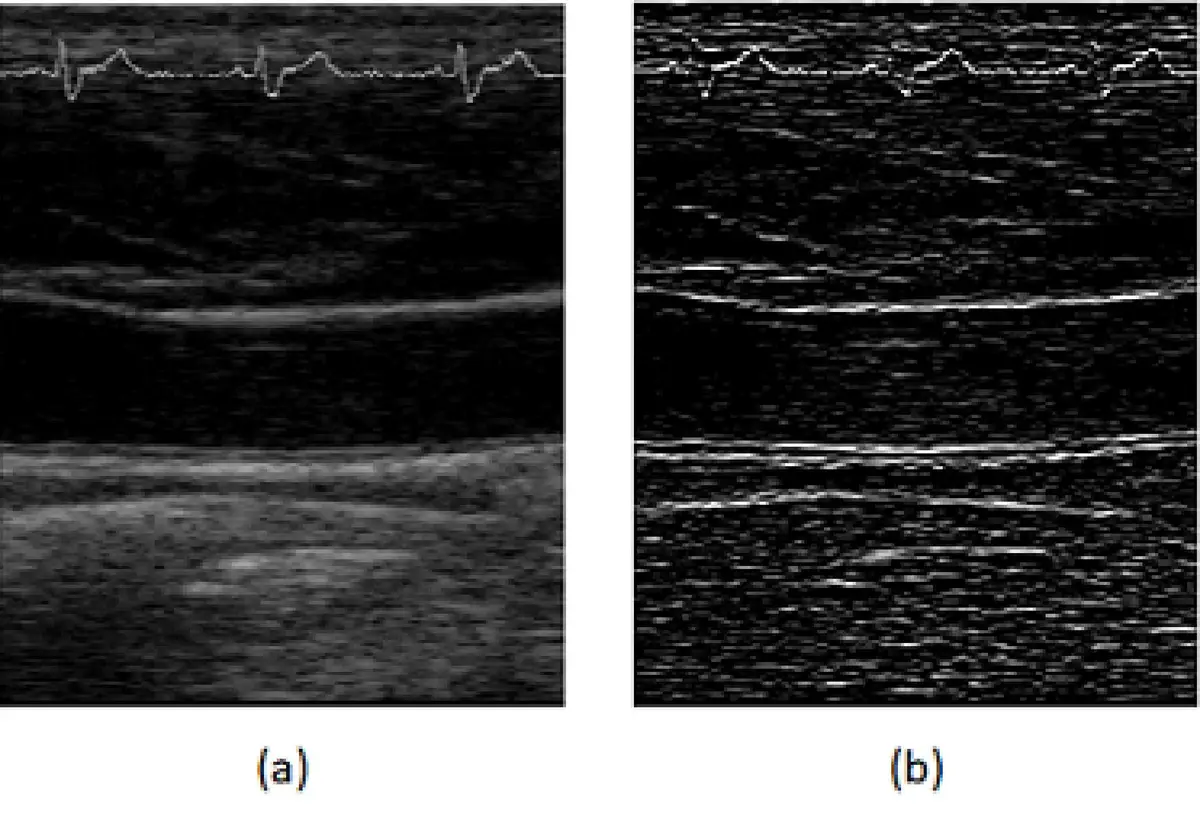

圖(a) 為B-mode 超音波頸動脈原圖,圖 (b) 為經下列何種數位濾波後之結果?

圖(a):B-mode 超音波頸動脈原圖(original image)。影像顯示頸動脈縱切面,可見血管壁(前壁、後壁)與管腔結構。影像呈現典型 B-mode 超音波特性:散斑雜訊(speckle noise)明顯,血管壁邊緣清晰度有限,灰階分佈較均勻柔和。

圖(b):經數位濾波後的結果。與圖(a)相比,圖(b)的視覺特徵明顯不同:

- 血管壁邊緣呈現強烈的高亮度線條,形成明顯的邊界對比

- 整體影像呈現高頻強化(high-frequency enhancement)的特徵

- 均一的組織區域趨近於黑色(低亮度),而邊緣過渡區則呈高亮

- 此為典型的**邊緣偵測(edge detection)或高通濾波(high-pass filtering)**結果